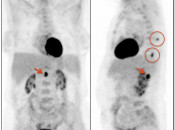

Value of the Sagittal PET Images:

- A careful review of these sagittal images is especially important to catch lesions involving the rectum, uterus and spine that can be easily overlooked with axial imaging alone. [Case 5] [Case 6] [Case 7]

Axial: 170-192 (not needed?) - Case 440: Met to spine and cord (hidden behind heart on coronal MIP)

Coronal MIP (see 1 met to cord, but miss 2nd cord lesion & spine met)

Sagittal MIP (see 2nd cord lesion and spine lesion)

Axial: PET 67-112; CT 90-149 (not needed?)